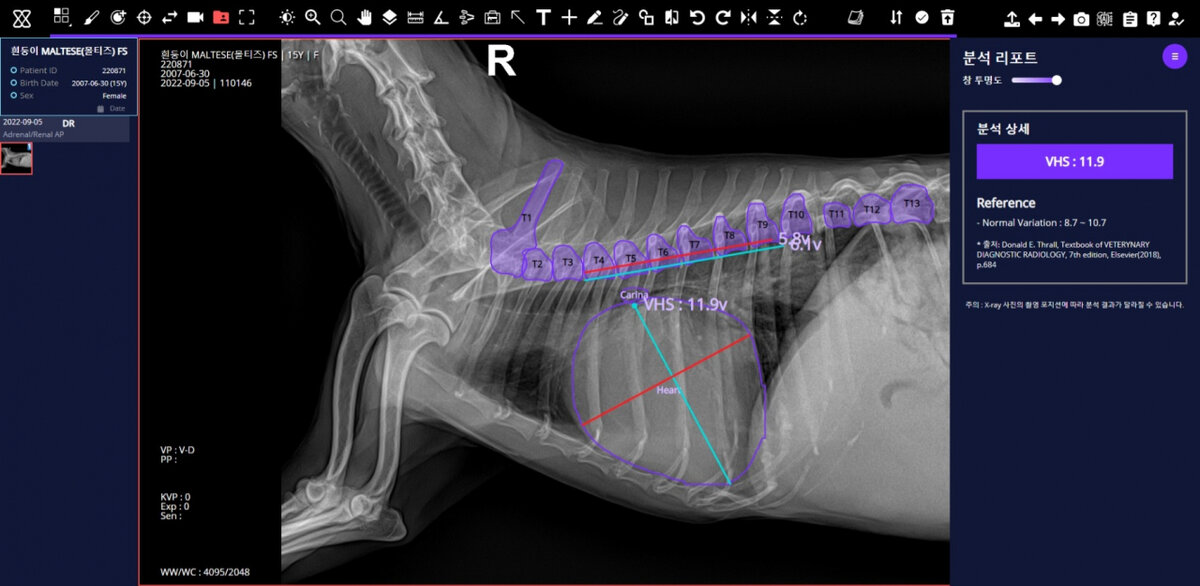

Решение с искусственным интеллектом под названием «X Caliber» предоставляет медицинские отчеты, когда ветеринар загружает рентгеновские снимки грудной клетки или опорно-двигательного аппарата собаки на веб-сайт сервиса. По данным SK Telecom, автономная диагностика занимает около 30 секунд.

Сервис диагностики ветеринарных изображений «X Caliber» на основе искусственного интеллекта от SK Telecom (SK Telecom)

По сравнению с диагнозом специалистов по ветеринарной визуализации в крупных ветеринарных больницах по всей стране, X Caliber показал 86-процентную точность в обнаружении заболеваний опорно-двигательного аппарата, 84-процентную точность в обнаружении аномальных структур в груди собаки и 97-процентную точность в измерении размера сердца.